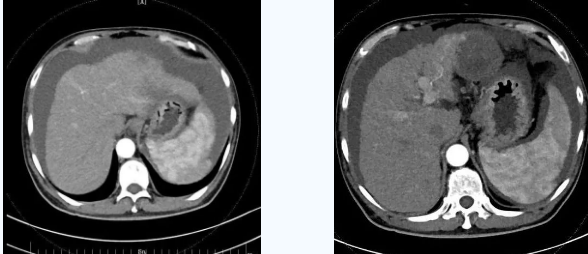

55歲的秦先生,于2021年10月被確診為肝癌晚期、慢性腎功能不全尿毒癥期,一直在口服靶向藥物進(jìn)行治療,規(guī)律行腎透析治療。直至今年4月因肝癌破裂出血行肝動(dòng)脈分支栓塞止血術(shù)后不久,秦先生開(kāi)始出現(xiàn)了反復(fù)大量腹水,只能先暫停癌癥治療,解決腹水問(wèn)題??墒乔叵壬奶幈疾▽めt(yī),腹水仍然沒(méi)有得到有效控制,于是在家人的多方咨詢打聽(tīng)下,慕名來(lái)到西安國(guó)際醫(yī)學(xué)中心醫(yī)院。

入院后,消化內(nèi)科五病區(qū)韓國(guó)宏院長(zhǎng)帶領(lǐng)團(tuán)隊(duì)對(duì)患者做了深入的檢查,檢查后發(fā)現(xiàn)患者“肝硬化失代償期、頑固性腹水、原發(fā)性肝癌、慢性腎功能不全尿毒癥期、2型糖尿病、高血壓2級(jí)”等病癥,韓院長(zhǎng)在對(duì)患者的病情進(jìn)行反復(fù)評(píng)估分析后表示,首先要明確患者目前腎透析后,仍然是大量腹水、無(wú)尿,那么腹水是肝源性的還是腎源性的,遂請(qǐng)多學(xué)科會(huì)診,結(jié)合相關(guān)檢查后明確,秦先生目前的大量腹水是由于門(mén)脈高壓導(dǎo)致的頑固性腹水,只有先解決門(mén)脈高壓導(dǎo)致的頑固性腹水,才可以繼續(xù)進(jìn)行癌癥治療,于是,韓院長(zhǎng)決定為患者實(shí)施TIPS手術(shù)。

由于大量腹水、晚期肝癌加上尿毒癥等的綜合病癥,手術(shù)難度和危險(xiǎn)系數(shù)都比平常增加了幾倍,面對(duì)這樣的情況,術(shù)前韓國(guó)宏院長(zhǎng)帶著團(tuán)隊(duì)反復(fù)分析討論,全面評(píng)估,在患者的各項(xiàng)指標(biāo)達(dá)到手術(shù)標(biāo)準(zhǔn)后,對(duì)患者實(shí)施了經(jīng)頸靜脈肝內(nèi)門(mén)腔靜脈分流術(shù)(TIPS),手術(shù)取得成功,術(shù)后患者恢復(fù)良好。

術(shù)后一個(gè)月秦先生來(lái)院復(fù)查,腹水已明顯較前減少,精神和飲食較術(shù)前明顯好轉(zhuǎn)。